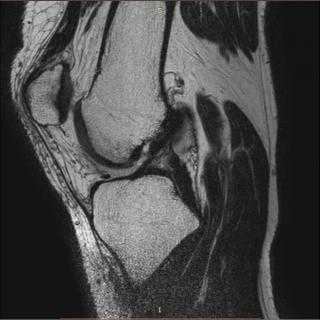

Из-за физики получения изображения кость лучше всего визуализируется на компьютерном томографе, а вот мягкие ткани и хрящевые образования лучше смотреть с помощью магнитно-резонансного аппарата.

МРТ коленного сустава также дает возможность получить трехмерную визуализацию колена и череду снимков, которые возможно посмотреть в отдельности, но здесь, в отличие от КТ, не используются рентгеновские лучи, и пациент не получает никакой дозы облучения. Для диагностического сканирования используется действие электромагнитных волн. В трубе томографа находятся большие магниты. Внутрь трубы помещается человек. Когда магниты включаются, создается электромагнитное поле. Частички организма пациента с содержанием воды начинают колебаться и излучать энергию. Эту энергию улавливает специальный компьютер. Таким образом магнитно-резонансный томограф рисует всю картину состояния мягких тканей и хрящей колена. Визуализация снимков на МРТ разносторонняя. Это необходимо для наиболее полного и точного осмотра коленного сустава и соседних структур.

Посредством магнитно-резонансной томографии лучше, чем с помощью КТ, видны мышцы, сухожилия, мениски, сосудистое русло и нервные окончания. МРТ коленного сустава будет приоритетным методом обследования, если есть подозрения на:

Магнитно-резонансная томография является методом выбора в вопросах диагностики кисты подколенной области или кисты Бейкера. Она позволяет достоверно выявлять характер сопутствующих внутрисуставных патологических изменений в коленном суставе, проводить дифференциальную диагностику, уточнять особенности анатомического строения и расположения кисты в подколенной ямке, а также локализацию ее соустья. Магнитно-резонансная томография при травмах коленного сустава позволяет с точностью до 90% оценить степень повреждения, сократить сроки постановки диагноза и тем самым увеличить эффективность лечения травматических повреждений коленного сустава.